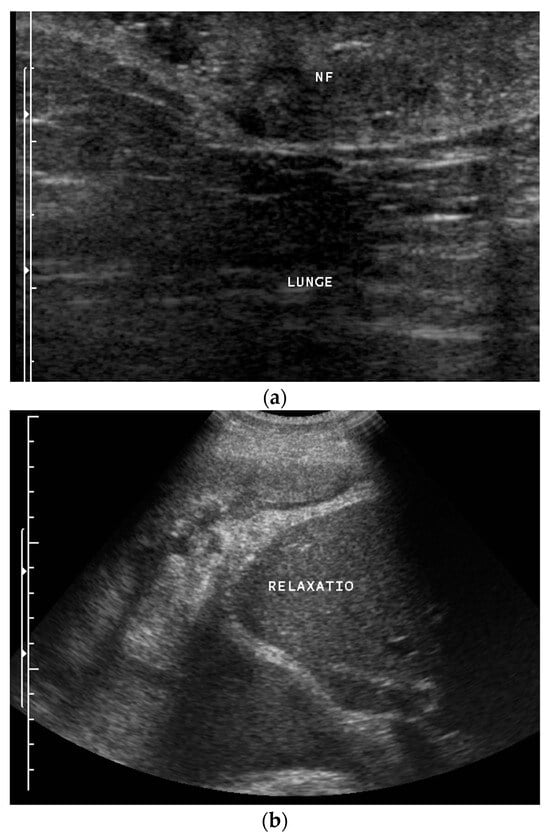

1. Introduction

2. Primary Pulmonary Sarcomas

3. Pleural Mesothelioma